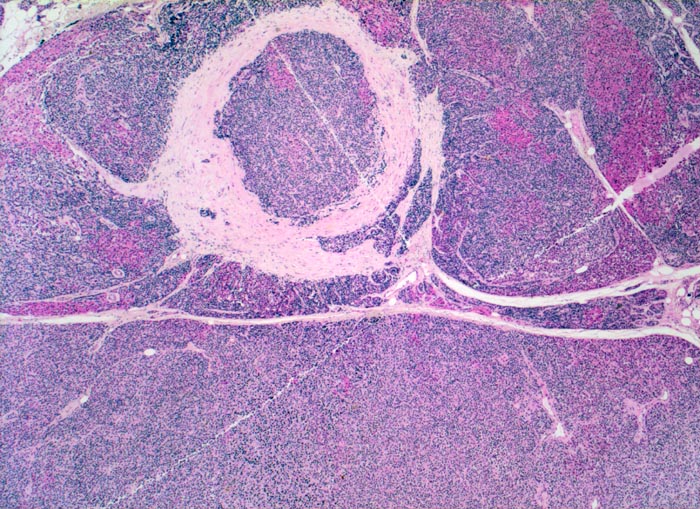

PathoPic – image database / PathoPic ID 5090 - noduläre Nebenschilddrüsenhyperplasie

noduläre Nebenschilddrüsenhyperplasie

Das Gewebe ist knotig strukturiert: die Knoten sind teils rötlich (onkozytäre Zellen), teils bläulich gefärbt. Im hyperplastischen Parenchym ist kein Fettgewebe erkennbar.

Bei der nodulären Hyperplasie sind alle Nebenschilddrüsen knotig vergrössert. Im Gegensatz zur Hyperplasie manifestieren sich Adenome der Nebenschilddrüse meistens als solitäre bekapselte Knoten. Im Randbereich von Adenomen findet man in 50% der Fälle nicht neoplastisches supprimiertes (atrophes) Nebenschilddrüsengewebe mit reichlich Fettzellen und verkleinerten Hauptzellen.